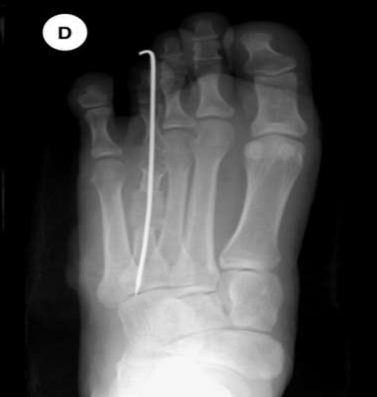

Fig: 1 The radiographs show an anteroposterior view of before and after operation of bone graft.

Figure 3